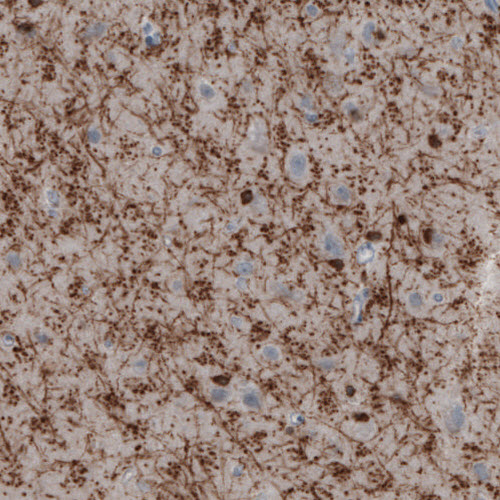

Immunohistochemical staining of rat cerebral cortex shows moderate immunoreactivity in oligodendrocytes.